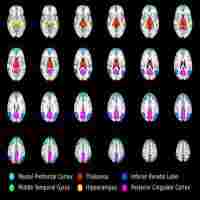

| Abstract | Mild cognitive impairment (MCI) is a transitional stage between normal aging and Alzheimer's disease (AD). Recent functional imaging studies have demonstrated regional deactivation magnitudes changes of default-mode network (DMN) in patients, accompanied by a defect of memory function. However, functional connectivity in the DMN during task performance was rarely investigated. METHODS : 26 amnestic MCI and 27 healthy controls underwent functional magnetic resonance imaging (fMRI) during an episodic memory task. Resting-state fMRI data were also collected. The changes in default-mode networks under both task-related and resting-state fMRI were obtained with a temporal correlation analysis. RESULTS: Significantly decreased functional connectivity was found mainly in anterior-posterior connectivity of DMN in aMCI groups. And a correlation existed between the anterior-posterior functional connectivity and MMSE scores. CONCLUSIONS: This study showed that disconnectivity of DMN could be used as an imaging biomarker for predicting the future cognitive decline of aMCI patients. |